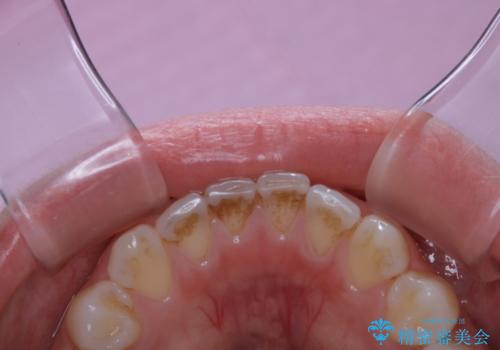

ワインによる着色・黄ばみをPMTCできれいに

- 前歯の着色・黄ばみを落としたい、とのことで来院されました。黄ばみや着色は前歯だけでなく、奥歯や裏表と全体的に付着していたため、PMTCの60分コースをご案内・ご相談し、行いました。